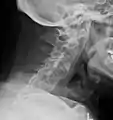

X-rays

The earliest changes demonstrable by plain X-ray shows erosions and sclerosis in sacroiliac joints. Progression of the erosions leads to widening of the joint space and bony sclerosis. X-ray spine can reveal squaring of vertebrae with bony spur formation called syndesmophyte. This causes the bamboo spine appearance. A drawback of X-ray diagnosis is the signs and symptoms of AS have usually been established as long as 7–10 years prior to X-ray-evident changes occurring on a plain film X-ray, which means a delay of as long as 10 years before adequate therapies can be introduced.[24]

Lateral X-ray of the mid back in ankylosing spondylitis

Lateral X-ray of the neck in ankylosing spondylitis